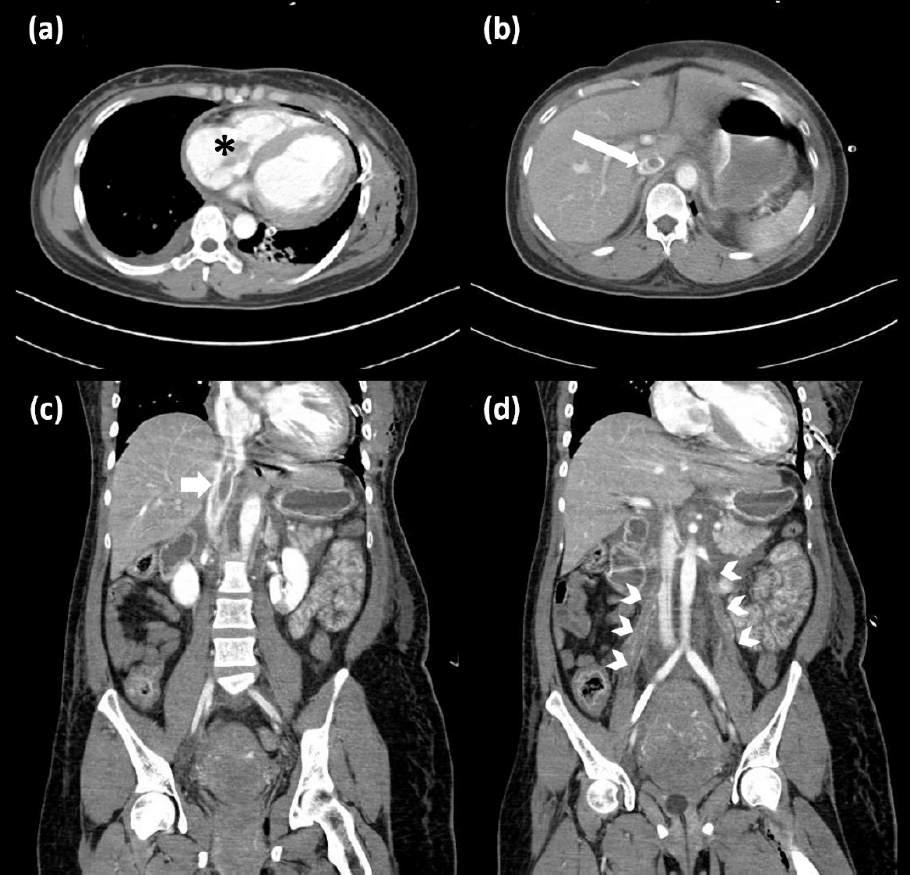

進一步全身電腦斷層發現靜脈系統多處 filling defect,包含右心房、下腔靜脈與卵巢靜脈(圖2)。和心臟科以及影像科醫師討論後,認為羊水栓塞和周產期心肌病變此兩鑑別診斷較為可能,但考量到產婦嚴重的心衰竭症狀,故最後以周產期心肌病變合併多處血栓作為主要診斷,並讓患者立刻接受葉克膜支持及 heparin 抗凝治療,但病情於 24 小時內惡化,最終死於心因性休克及瀰漫性血管內凝血DIC導致的多處出血。

圖2 (a) 星號所示右心房內血栓;(b)(c)長箭頭所示下腔靜脈內血栓。 (d)箭頭所示卵巢靜脈血栓。

本圖取自 Chiu P-W 等人發表於 Annals of Emergency Medicine (2023),經 Elsevier 授權重製